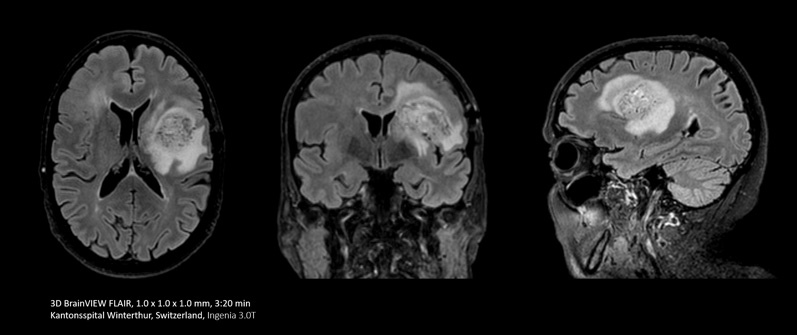

Bei einigen Untersuchungen, beispielsweise von Gehirn und Wirbelsäule, lässt eine hohe räumliche Auflösung sehr kleine Nerven und Gefäße besser erkennen. Um diese Auflösung zu erreichen, können mit Compressed SENSE 2D-MR-Scansequenzen durch schnellere 3D-Sequenzen ersetzt werden.

Mit Compressed SENSE lässt sich ein 2D-FLAIR-Scan mit einer Ausrichtung durch einen volumetrischen 3D-FLAIR-Scan mit mehreren Ausrichtungen ersetzen. Die Scandauer beträgt dabei lediglich dreieinhalb Minuten.

Ich erstelle häufig Bilder des Gehirns. Bisher haben wir die FLAIR-Sequenz mit einer Schichtdicke von 5 mm verwendet. Mit Compressed SENSE können wir jetzt einen volumetrischen 3D-Scan statt in sechs Minuten in etwa dreieinhalb Minuten durchführen.“

Dr. Mark Oswood, MD, PhD, Neuroradiologe, Hennepin Healthcare, Minneapolis, USA